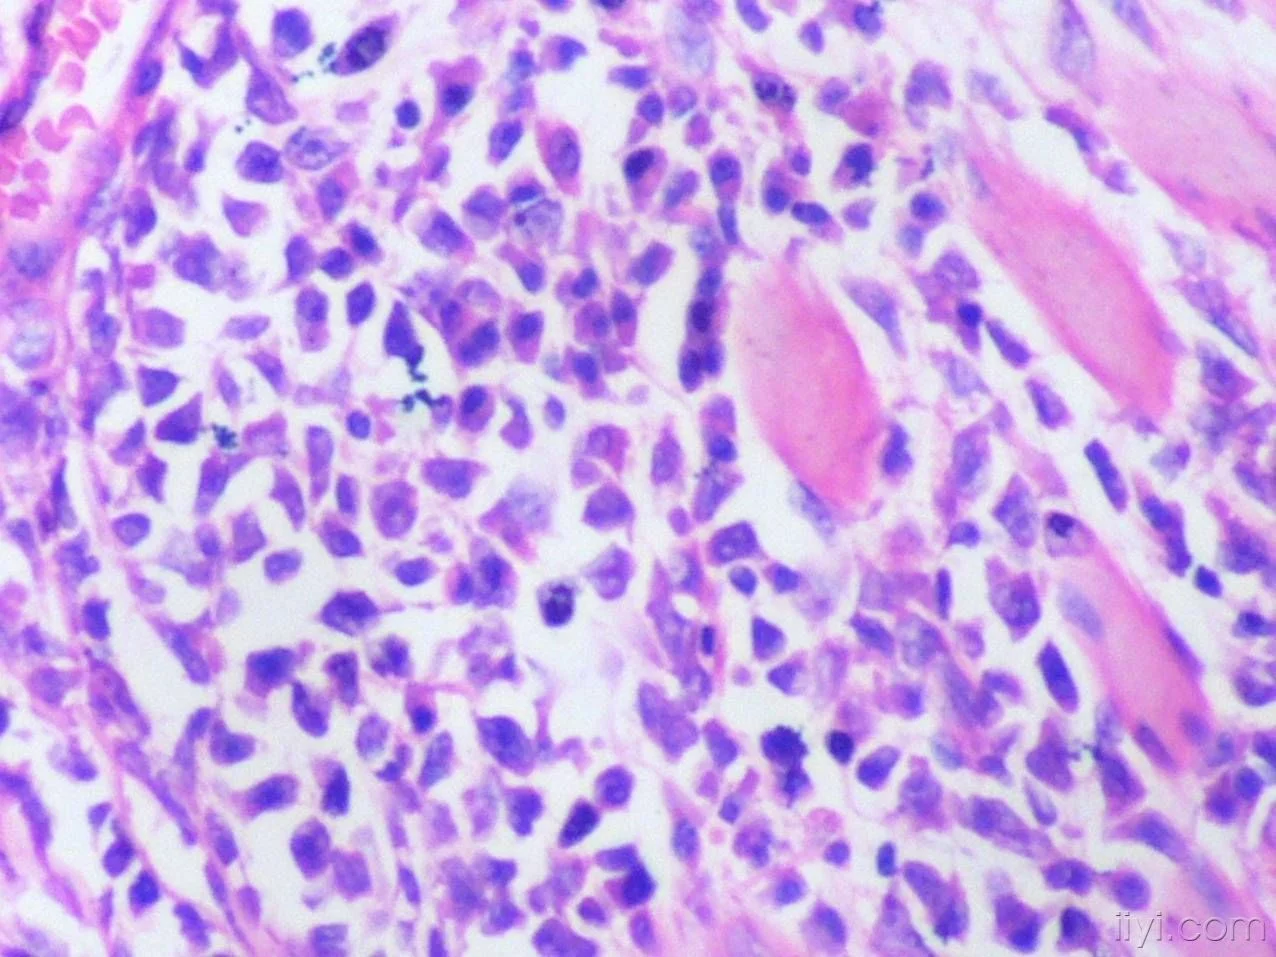

骨细胞是骨组织的主要细胞。

破骨细胞

破骨细胞具有特殊的吸收功能,某些局部炎症病灶吸收中,巨噬细胞也参与骨吸收过程。

骨祖细胞

位于骨膜内,是骨组织中的干细胞,细胞小,呈梭形,胞质少,弱嗜碱性,核椭圆形。骨祖细胞着色滑物白料正伯护期浅淡,不易识别。骨祖细胞能分化成为成骨细胞和成软骨细胞,来自分化方向取决于所处局部微环境和所受刺激性质。